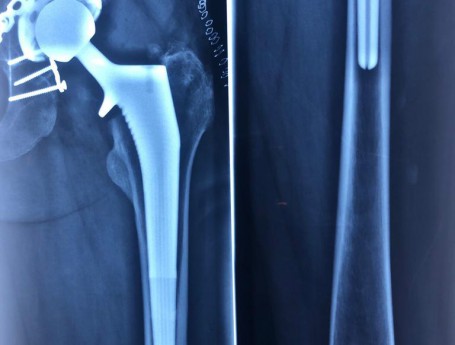

Revision Total Hip Arthroplasty

Revision Total Hip Arthroplasty Femoral Stem